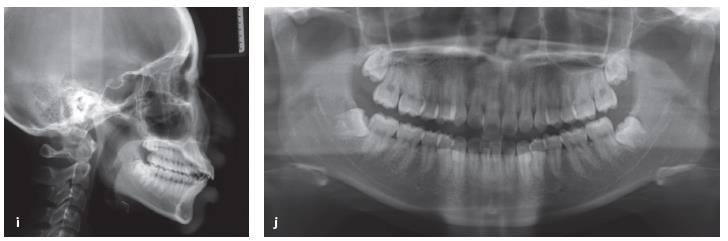

Một bệnh nhân nữ 17 tuổi có sai khớp cắn loại II với sự nhô ra của hàm trên và hàm dưới và chen chúc nhẹ (Hình 13-16a đến 13-16j).

Hồ sơ trước xử lý. Bệnh nhân có một sai khớp cắn loại II với hàm trên và hàm dưới nhô trước và chen chúc ít